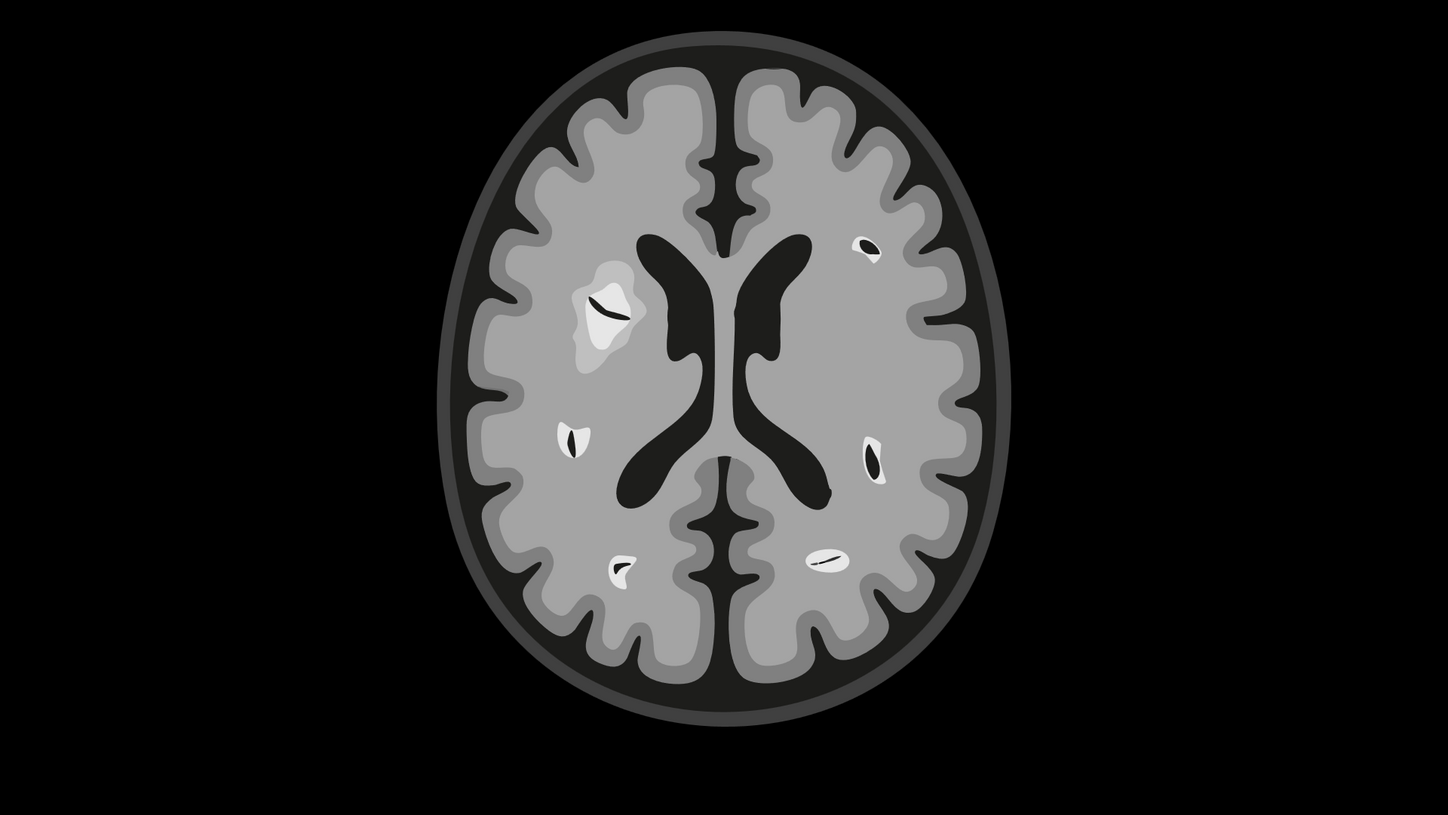

White Matter Hyperintensities (WMH)

As an autoimmune disease, MS is characterized by an overactive immune system, resulting in inflammation areas that lead to the loss of myelin insulation of nerve cells. These active inflammation areas can be seen in MRI on T2-weighted TSE imaging, primarily in the T2 FLAIR contrast. They manifest as hyperintensities, meaning areas with enhanced brightness. As MS patients undergo regular MRI scans to follow-up the disease, these lesions appear at different spatial locations in the brain (dissemination in space, see below). However, as a confounder, such hyperintense areas do not only result from MS, but also from other root causes and sometimes require additional contrasts (e.g., MPRAGE or T2*/SWI) to rule out differential diagnoses.